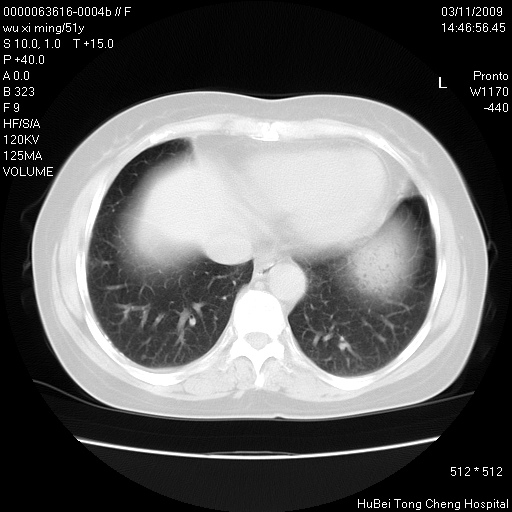

患者 女,51岁。因“胆囊炎,胆囊结石”,行常规术前胸部x线检查发现:右上肺结节病灶,建议行进一步检查。患者无咳嗽、咳痰及咯血等呼吸道症状,近期出现背部疼痛不适。

胸部ct轴位平扫(层厚10mm,螺距1.5,重建间隔10mm;部分层面:层厚3mm,螺距1.0,重建间隔3mm),图像如下:

1、周围型肺癌。(毛刺正、血管束集征,分叶。)

集束征,胸膜牽拉征,毛刺,淺分葉高度提示ca.

右肺周围型肺癌伴肺内转移及胸椎转移。已无手术机会。